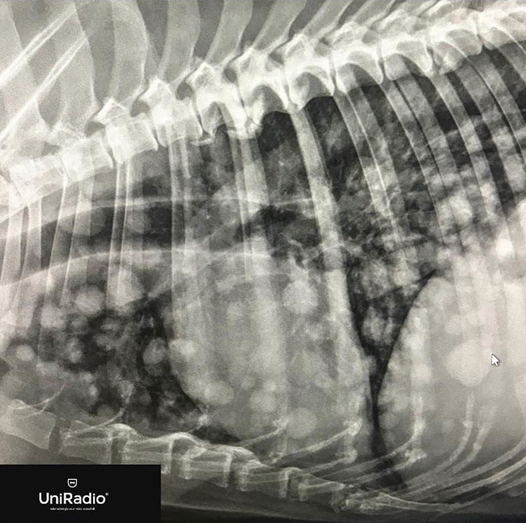

Nodular pattern

multiple rounded opacities

- bronchopneumonia with pre-existing pleural effusion

- the lung has no well-defined margin

With very observable radiopacity nodules

Tuberculosis

Metastases